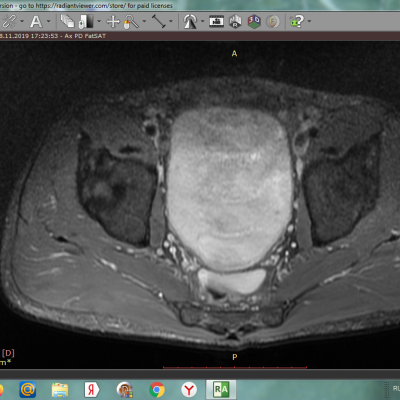

на мрт тазобедренного сустава обнаруженно .серацеле или киста в районе мюллерового протока , достаточно большая , никто до конца не может сказать что это